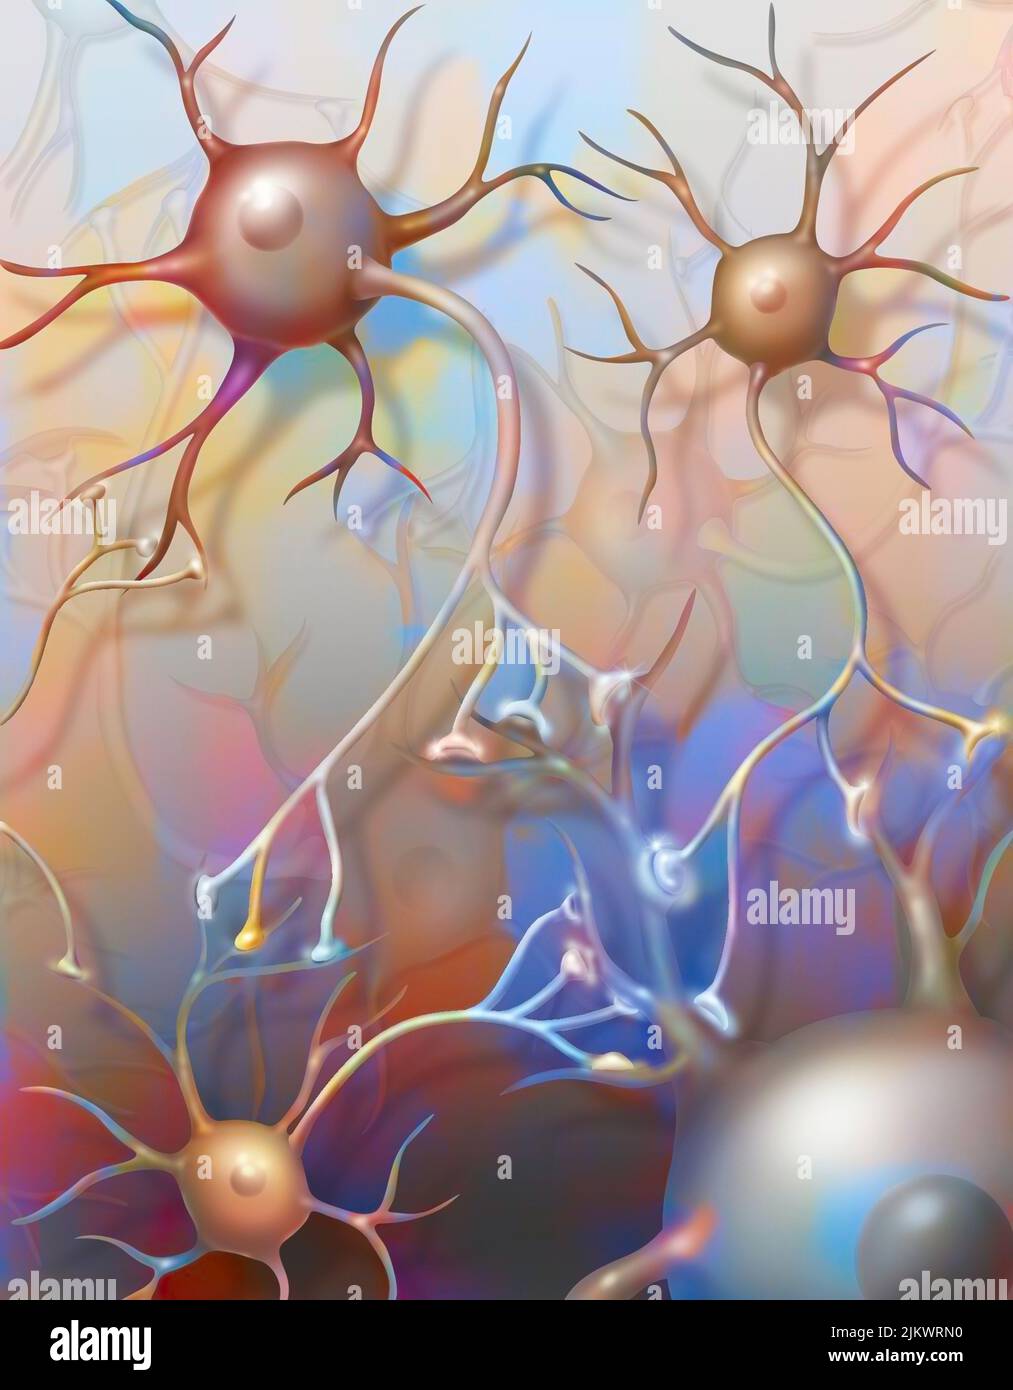

RF2JKWRF2–Pla (potentialisation à long terme) après une semaine, étape 2 : la synapse est stimulée avec une plus grande efficacité.

RF2JKWR03–Action des sels minéraux et des vitamines sur la transmission des impulsions nerveuses aux synapses.